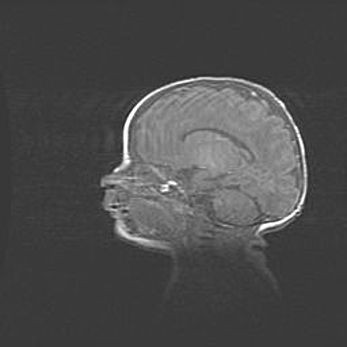

Церебральная ишемия II.

Возраст: 5 дней

Вес: 3400 г

Пол: женский

Окружность головы: 35 см

Срок гестации: 39 недель

Церебральная ишемия – это заболевание, характеризующееся недостаточностью (гипоксией) либо полным прекращением (аноксией) снабжения мозга кислородом по причине закупорки одного или нескольких сосудов. Это приводит к  что метаболическим расстройствам различной степени тяжести в тканях головного мозга, развитию коагуляционных некрозов и гибели нейронов.